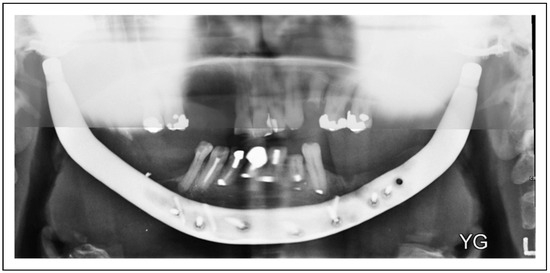

Bilateral TMJ Replacement With Complete Replacement of the Mandible, Patient 8